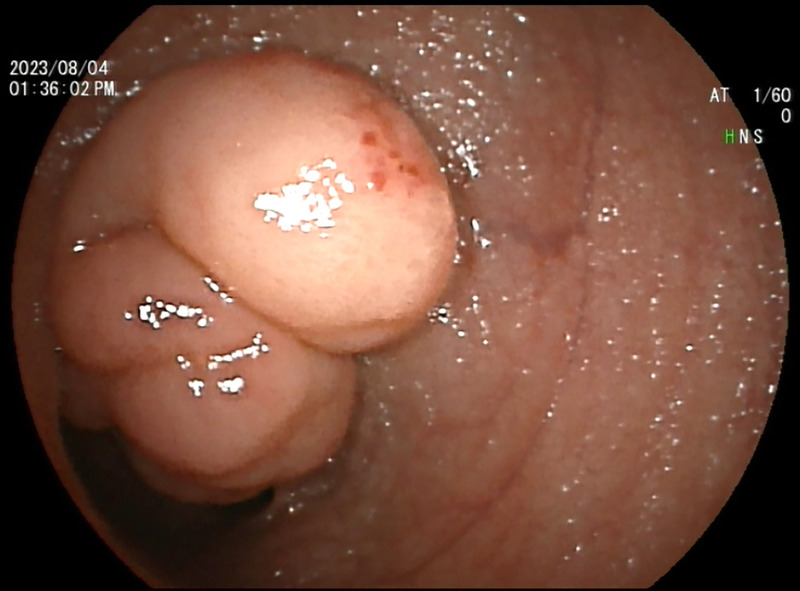

A rare but interesting case of small intestinal tumor diagnosed by transrectal EUS-FNA (with video).